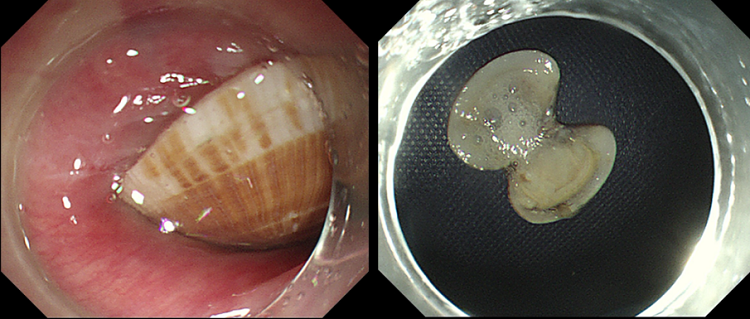

4小时后,一场内镜下的取花蛤手术紧急展开。

多科室协同下,林芬副主任医师执镜操作,当胃镜进入食道,只见一个花蛤嵌顿于食道上段。手术过程比想象得更加困难,稍有不慎边缘锐利的花蛤壳就可能会划破脆弱的食道,造成食道出血、穿孔。林芬副主任医师小心翼翼用异物钳钳持花蛤的一端,通过异物钳调整花蛤方向后,快速、精准的将花蛤壳取出。仅用时大约2分钟,最终卡在张大妈食管处、长达2.3厘米边缘锋利的完整花蛤被取出来了!林芬副主任医师再次进镜观察,手术过程顺利,未造成食道损伤。手术结束后,患者家属对消化内镜中心、麻醉医护团队的高超技术及勇于担当的精神深表感激。